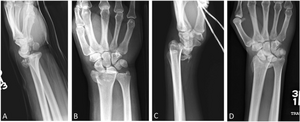

A Barton fracture is a type of wrist injury where there is a break of the front or back of the radius nearest the hand, resulting in the wrist being pushed out of place.[1] It typically occurs after falling on on top of a bent wrist.[2]

There exist two types of Barton's fracture – dorsal[3] and palmar, the latter being more common. The Barton's fracture is caused by a fall on an extended and pronated wrist increasing carpal compression force on the dorsal rim. Intra-articular component distinguishes this fracture from a Smith's or a Colles' fracture.

Treatment of this fracture is usually done by open reduction and internal fixation with a plate and screws, but occasionally the fracture can be treated conservatively.[citation needed]

Additional images[edit | edit source]